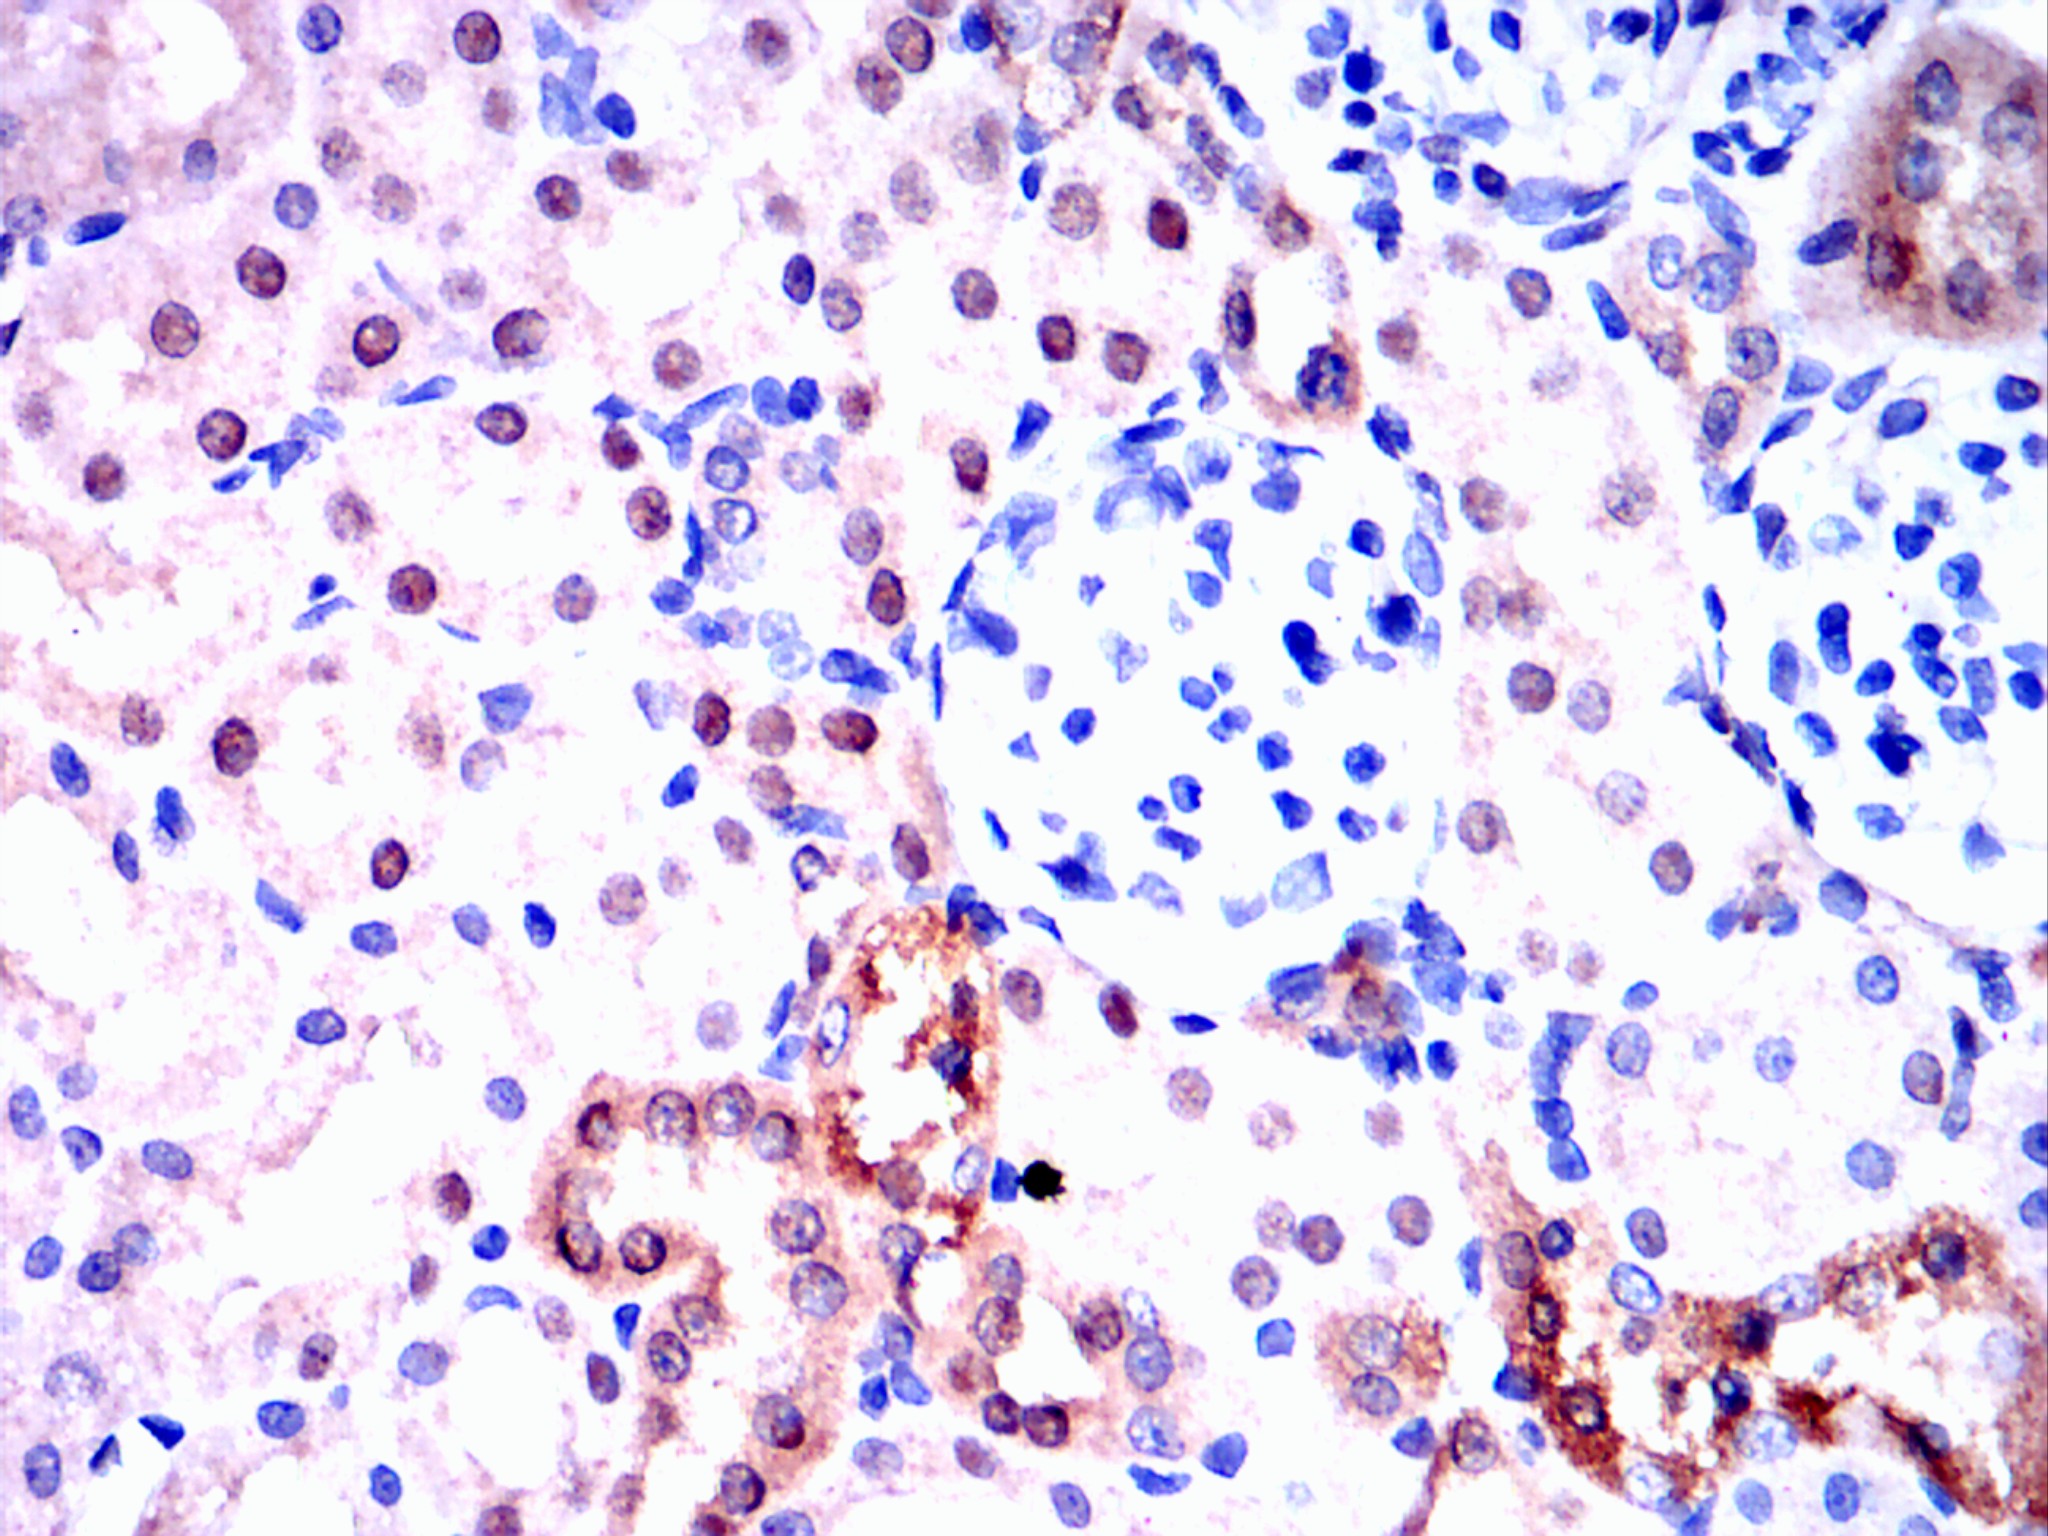

Immunohistochemical analysis of paraffin-embedded rectum cancer tissues using Visfatin(PBEF) mouse mAb with DAB staining.